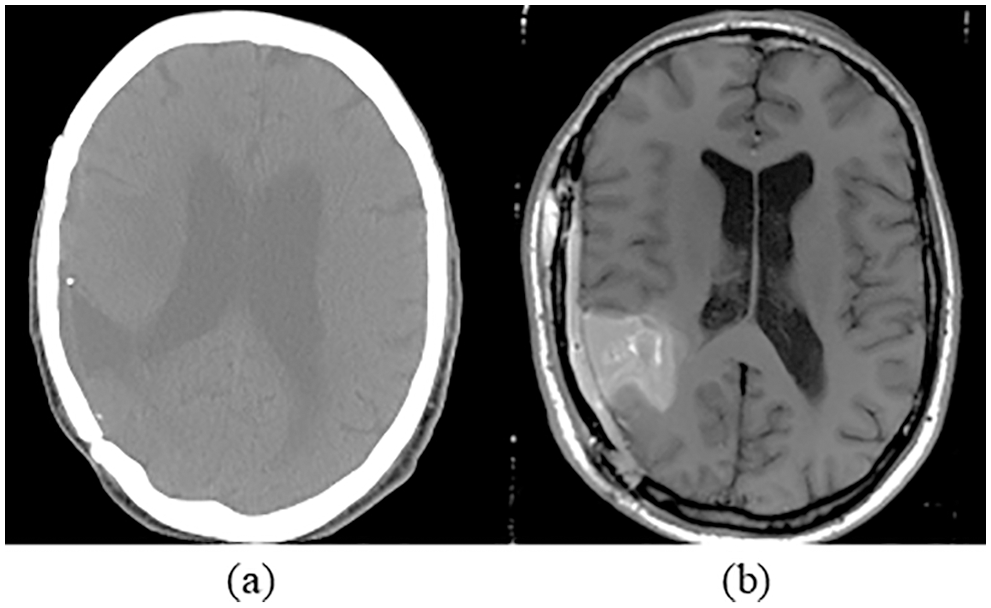

615 patients with 615 CT and MRI brain images were used in the research work. These pre-registered images are gathered from a publicly available database by Harvard Medical school [27]. The source images are grouped into training data and testing data sets. The training data consists of 369 images, including 105 benign and 264 malignant, whereas testing data consists of 246 images, including 99 benign and 147 malignant tumor images. Samples of MRI and CT images are shown in Fig. 4. Fusion of MRI and CT is performed to get a clearer view of the brain. The resultant image information is better visible than individual CT or MRI. The developed brain tumor classification method is implemented in the MATLAB2019 platform and executed on an intel core i5 processor with 12 GB memory.

Figure 4: Sample of brain images (a) CT image (b) MRI image